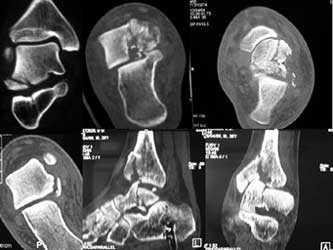

Перелом пяточной кости обычно происходит вследствие компрессии на подтаранный сустав между таранной костью и землей. Линия перелома проходит косо через заднюю таранную суставную поверхность (рис. 4). При этом образуется два основных внутрисуставных отломка: передневнутренний (сустентакулярный) и задненаружный. Сустентакулярный фрагмент прочно крепится к таранной кости межкостной связкой пазухи предплюсны. Фиксирующая роль передневнутреннего отломка имеет принципиальное значение. Одна из основных задач травматолога сводится к сопоставлению с ним свободного задненаружного фрагмента.

Вне зависимости от способа предполагаемой фиксации отломков — внутрикостного или внекостного — существует ряд клинически актуальных вопросов, на которые компьютерная томография может дать однозначные ответы.

Прежде всего это касается количества внутрисуставных отломков. Прогноз лечения ухудшается, если визуализируются более двух фрагментов.

Второй важный аспект — близость линии перелома к медиальной поверхности пяточной кости. Наихудший прогноз имеют переломы, проходящие через пазуху предплюсны. Фиксация обоих фрагментов к таранной кости может оказаться недостаточной для полноценного функционирования суставов.

В отличие от сустентакулярного отломка задненаружный, как правило, имеет подвывих по отношению к таранной кости, плоскостное и угловое смещение. Точное количественное их измерение при КТ конкретизирует задачу травматологу при фиксации отломков.

При внутрикостном остеосинтезе при боковом доступе важно заранее знать, будет ли задненаружный фрагмент скрыт латеральной стенкой тела пяточной кости. Их взаиморасположение лучше визуализируется в коронарной плоскости (рис. 5).